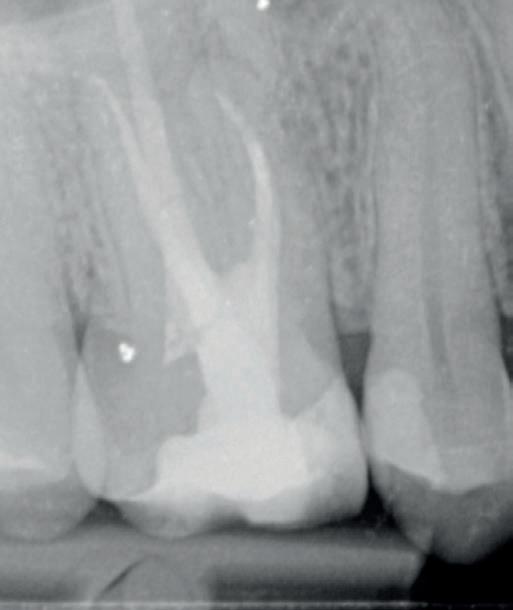

Deze opleiding heeft als doel om de mondhygiënist (ook niet Nederlands gediplomeerd), zo op te leiden dat ze cariës kunnen diagnosticeren en plastische restauraties kunnen vervaardigen. Er zal aandacht worden besteed aan de theorie achter deze behandeling, er zal preklinisch geoefend worden en er zullen klinische verrichtingen uitgevoerd worden tijdens een een klinische stage.

Tijdens deze 5 -daagse opleiding wordt aandacht besteed aan het periodiek mondonderzoek met betrekking tot cariës en röntgendiagnostiek, prepareren en restaureren. Prepareren en restaureren wordt geoefend op fantoom en de opleiding wordt afgesloten met patiënt behandelingen. Tijdens deze opleiding zal duidelijk worden welke behandelingen geschikt zijn voor de mondhygiënist en worden valkuilen besproken. Praktische vaardigheden, maar ook theoretische kennis komen ruimschoots aan bod. Hoe zorg je voor een functioneel en esthetisch goede vulling?

Behandelen van patiënten

Om de opleiding af te ronden is het nodig om een enkele patiënten te behandelen. Deze moeten door de cursist zelf worden meegenomen. Dit moeten patiënten zijn met primaire cariës. Je kunt bitewings meenemen op de 1e of 2e opleidingsdag om te bespreken of het geschikte caviteiten zijn. Als de behoefte of vraag er is, kunnen we het programma iets aanpassen aan de omstandigheden. Een echte op maat gemaakte opleiding dus!

De opleiding wordt afgesloten met een theoretische en praktische toets.

• Diagnose: aandachtspunten bij het mondonderzoek, inschatten van het cariësrisico en frequentie van bitewings

• Indicatie: wat behandel je (nog) niet en wat wel, wanneer stuur je iemand door naar de tandarts

• Interpretatie van bitewings: wanneer behandelen en wanneer niet; bijzondere gevallen

• Prepareren: gangbare preparatie technieken

• Vullen en afwerken: materiaalkennis en matrixsystemen

• Moderne inzichten in omgaan met composiet en bonding

• Praktische vaardigheden: aanbrengen van cofferdam en oefenen op fantoom (naar behoefte)